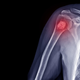

Pri kostnem raku je lahko govora o več različnih rakih, ki se razvijejo v kosteh. Rak, ki se začne v kosti, imenujemo primarni kostni rak. Tumorji, ki se začnejo v …

Prepoznate kostnega raka? Potem ko je našo regijo pretresla novica, da je za kostnim rakom zbolel priljubljeni pevec Jasmin Stavros, smo podrobneje pogledali simptome raka na kosteh in kostnega tumorja. …